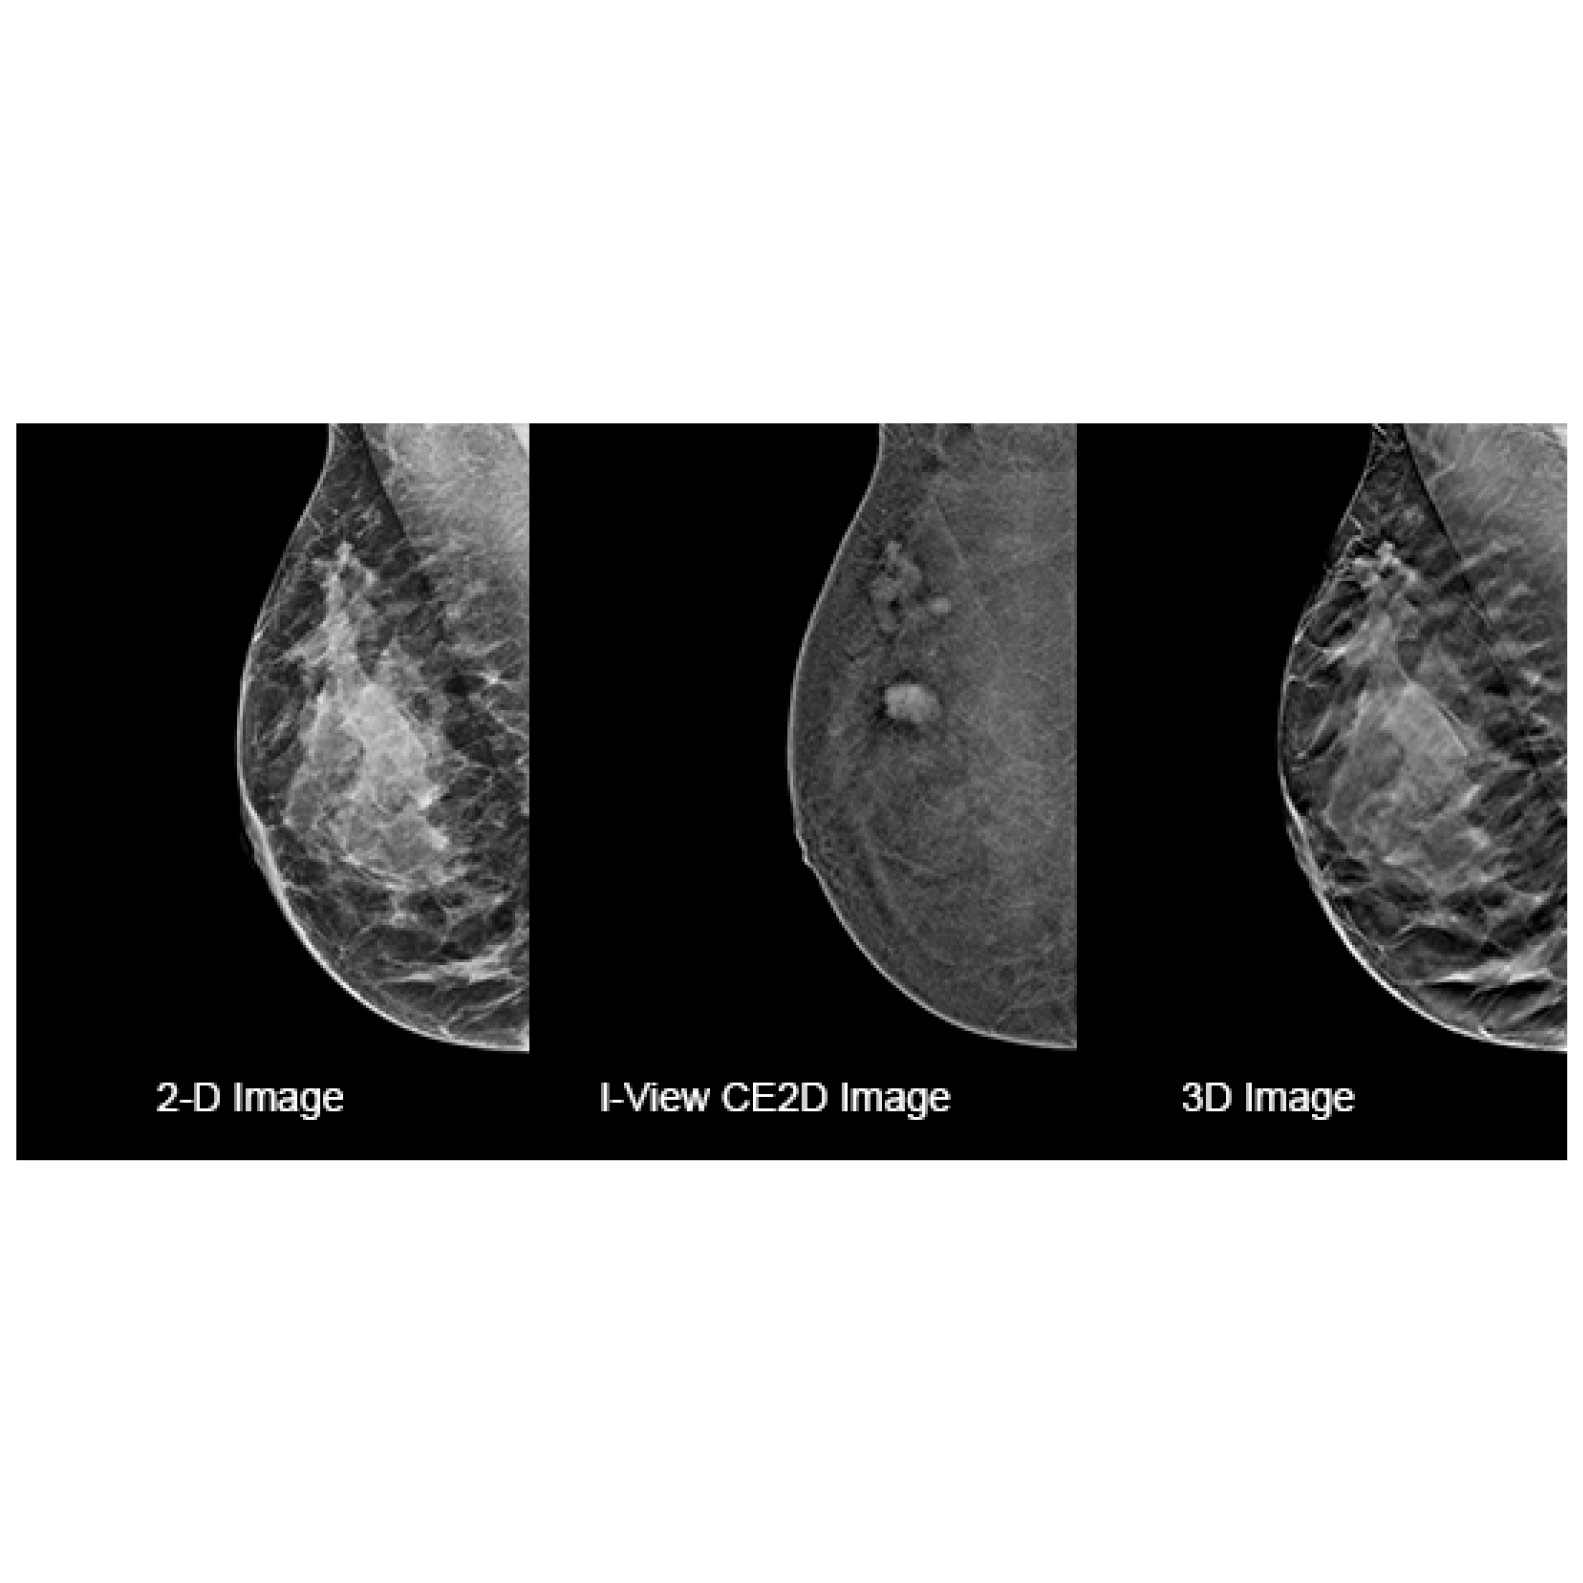

Affirm Contrast Biopsy software allows targeting and acquisition of tissue samples in lesions identified on prior CEM exams, where a correlate may not be found using tomosynthesis or ultrasound.

During a contrast enhanced mammogram, following iodine injection, lesions are localized using a scout view and the 15-degree image pairs.

Turn the invisible into visible by using functional imaging.